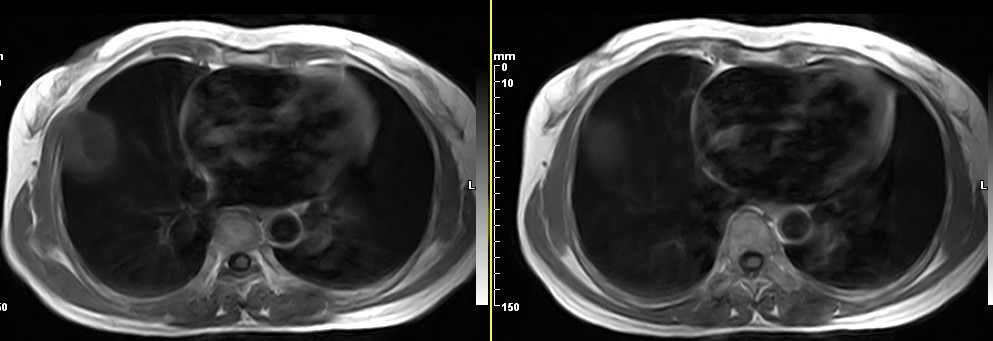

女,49岁。三年前因胸部不适在外院行CT检查诊断报告:右胸壁占位病变,考虑胸膜间皮瘤可能性大。现病人到我院检查了解情况。算是较典型的病变吧?大家看看MR比CT优点在哪里?

病检神经鞘瘤

液性信号符合神经鞘瘤囊变。